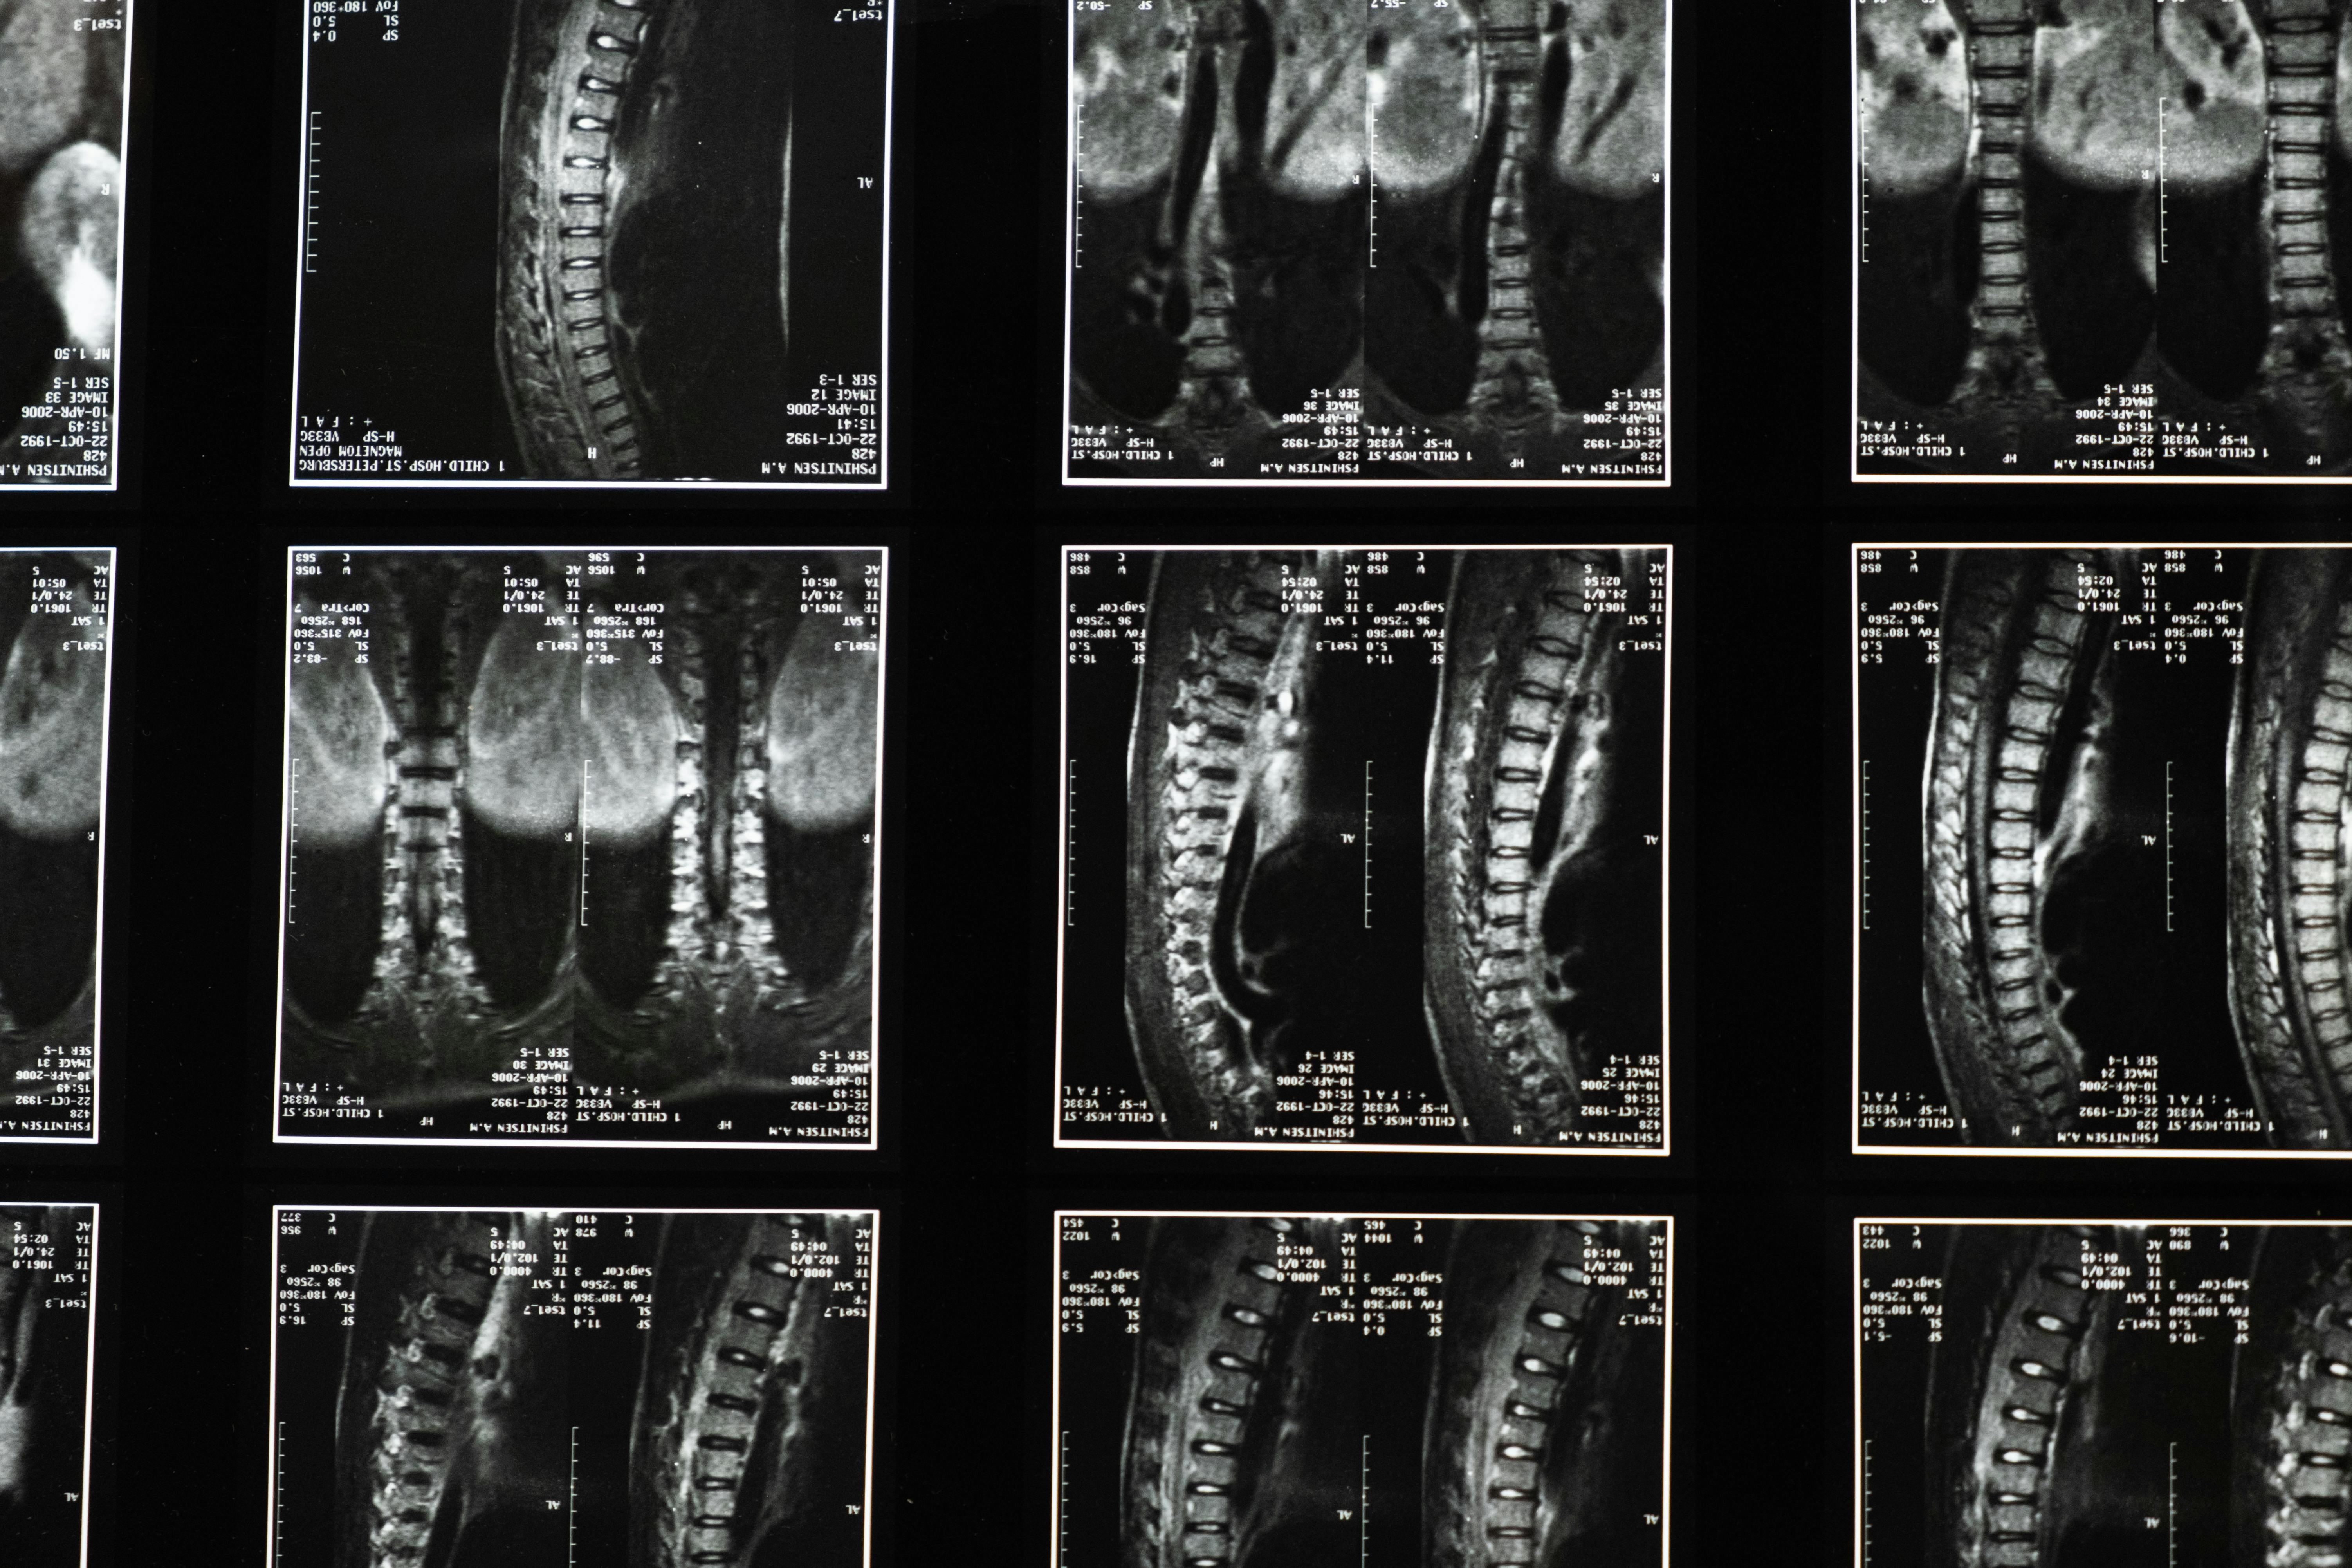

Lumbar Spinal Stenosis

Lumbar spinal stenosis is a condition describing the narrowing of the area in the lower spine responsible for carrying nerves to the lower extremities. This area is very small, and it becomes even smaller when surrounding bone and tissue grows. Accidents, arthritis, and general wear and tear on the spinal bones and joints play a significant role in lumbar spinal stenosis. When the lumbar canal is restricted, the nerves traveling through it become squeezed, resulting in back pain as well as leg pain and weakness. Many adults knowingly and unknowingly suffer from this form of stenosis.

Sciatica

Back conditions, such as sciatica, often lead to leg pain as well. Sciatica is an inflammation of the sciatic nerve, which begins in your lower back and travels down to your legs and feet. While sciatica can be difficult to diagnose and its symptoms sometimes diminish on their own, it is often the result of spinal stenosis. Sciatica and other spinal conditions may develop gradually, or they may come on suddenly. Much of the time, what once was tolerable turns into an acute issue. Arthritis or injury can lead to an acute development of sciatica as well.